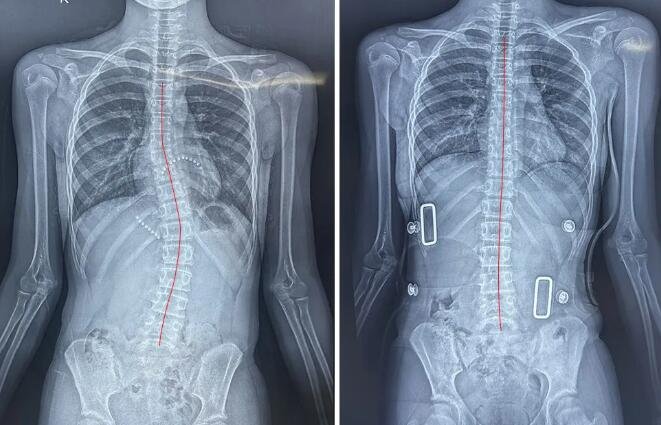

13岁少年脊柱形态调整前(左图)、1个月调整课后(右图)